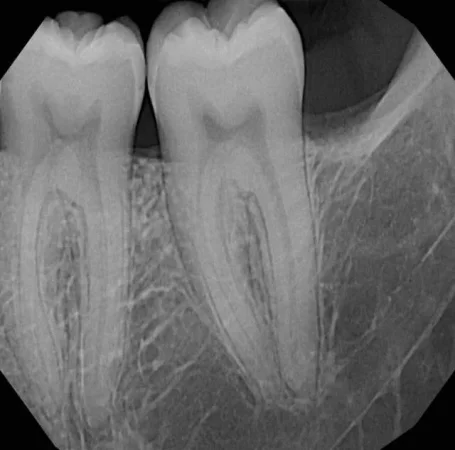

Shitet grafi dentare panoramex dhe cefalometri sirona xg 3d. Prodhim i vitit 2016 . Nje vit garanci Cel. : 0683869777

Shitet Panorameks 2D/2D+ Carestream (Kodak) Aparati është në gjendje shumë të mirë si nga ana vizuale dhe nga ajo funksionale. Ka edhe opsionin...